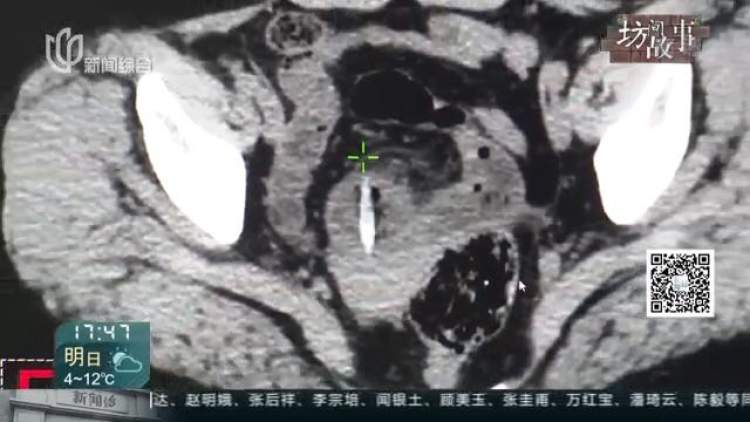

当时的腹部CT显示,在马女士的肠道里有锥状物体,已经刺破肠壁,引发了局限性腹膜炎,但马女士仍不知究竟是什么引发的,更没想到肚子里的竟是枣核。

考虑到情况危急,医生立即对她进行了手术,结果发现原来是一颗枣核,长度竟有3.5厘米长。